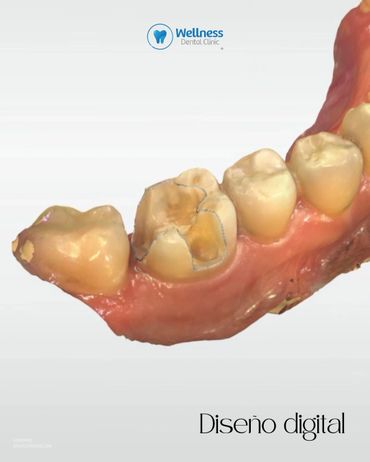

En Wellness Dental Clinic utilizamos tecnología de última generación para ofrecer restauraciones precisas, estéticas y duraderas. 🦷💙 Este procedimiento se realizó en un solo día, con una duración aproximada de dos horas. 🔹 Proceso realizado: 1. Preoperatoria – Evaluación inicial de la pieza. 2. Preparación – Eliminación de caries y conformación del diente. 3. Diseño digital en CEREC – Modelado personalizado de la incrustación. 4. Fresado – Fabricación de la restauración en cerámica de alta resistencia. 5. Prueba y ajuste – Revisión de puntos de contacto y adaptación. 6. Cementado – Colocación definitiva. 7. Pulido final – Integración estética y natural. 8. Resultado final – Función y estética recuperadas. Cada paso fue realizado bajo protocolos de precisión y seguridad, logrando un resultado completamente personalizado para nuestro paciente. ✨ 📲 Agenda tu valoración y descubre la experiencia Wellness. 📍 Independencia #1118 – Local 12, Piso 4, Zona Urbana Río Tijuana 📞 664 208 9300 | 📱 WhatsApp: 664 477 4313 🌐 wellnessdentalclinic.us 📧 wellnessdentalclinictj@gmail.com